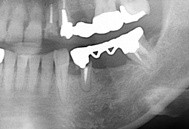

この患者さんですが、ブリッジが噛むと違和感がある、ということで来院されました。

レントゲン写真を撮ってみると何と片方の歯がブリッジから外れてしまっている状態でした。

その中で1本外れてしまっていても、患者さんにとっては分かりにくい場合もあります。

そして気がつかないうちに外れてしまった歯がだめになってしまうこともあります。

この患者さんは結局だめになってしまった歯は抜いて、インプラントになりました。